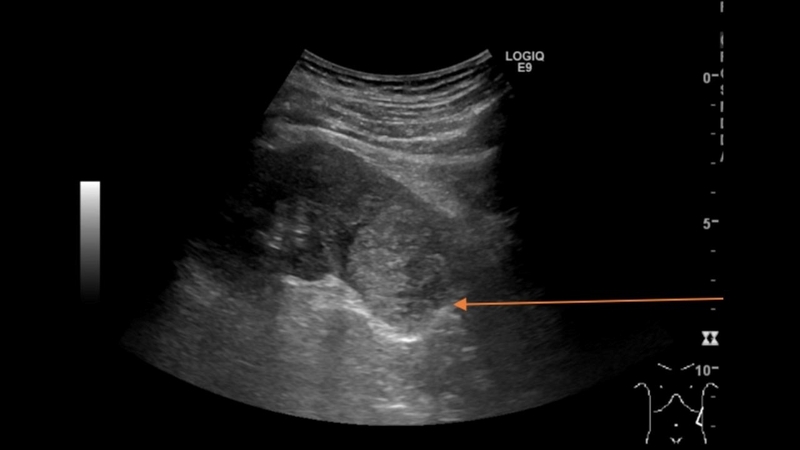

Siêu âm là phương pháp chính để xác định thận ứ nước và phân mức độ bệnh, vì nó an toàn, không xâm lấn, có độ chính xác cao. Mục đích của siêu âm là phát hiện các bất thường ở thận, bàng quang và hệ tiết niệu, cũng như tìm ra nguyên nhân bệnh tiềm ẩn.

Tuy nhiên, trong một số trường hợp, siêu âm có thể không đủ để xác định nguyên nhân cụ thể. Lúc này, bác sĩ có thể yêu cầu thêm các phương pháp hình ảnh như chụp X-quang đường niệu, CT scan hoặc MRI để xác định vị trí tắc nghẽn.